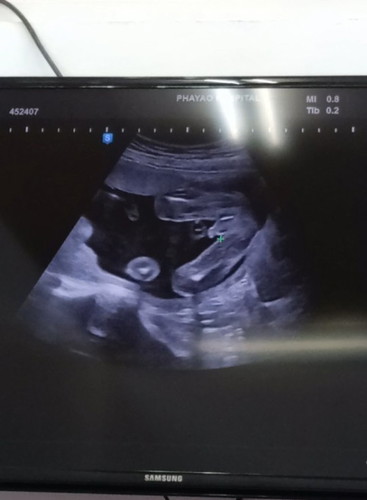

คุณหมอบอกลูกชายมากว่า 90%

ผู้ชายค่ะ ซาวด์ตอน 19 สัปดาห์คะ ผลนิฟก็ผู้ชายคะ สมใจครอบครัวมากทท